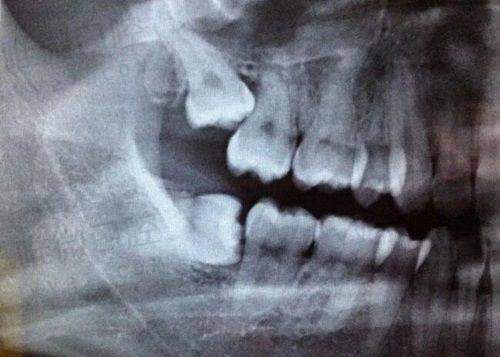

种植牙讲究精度,医生手稳是一方面,精良设备的辅助也非常关键。海涛口腔在这方面一点都不吝啬,引进了德国Kavo卡瓦CT扫描仪、种植机、3D导板导航系统等高端设备。

这些设备可以实现术前口腔全方面数字化分析,医生可以提前知道牙槽骨的密度、神经位置,做到“种植体避雷超精细”。而且用导板制定手术路径,整个过程创伤小、修复快。

这里的医生会通过诊断拍片结合面型、吞咽咬合力量、牙槽骨情况来设计种植方案。例如,有些人牙槽骨高度不足,传统植骨手术复杂,但海涛可通过“穿颧植入”这种微创方式巧妙解决;还有患者怕痛,这里也能安排舒适局麻或微痛镇静方案种牙。